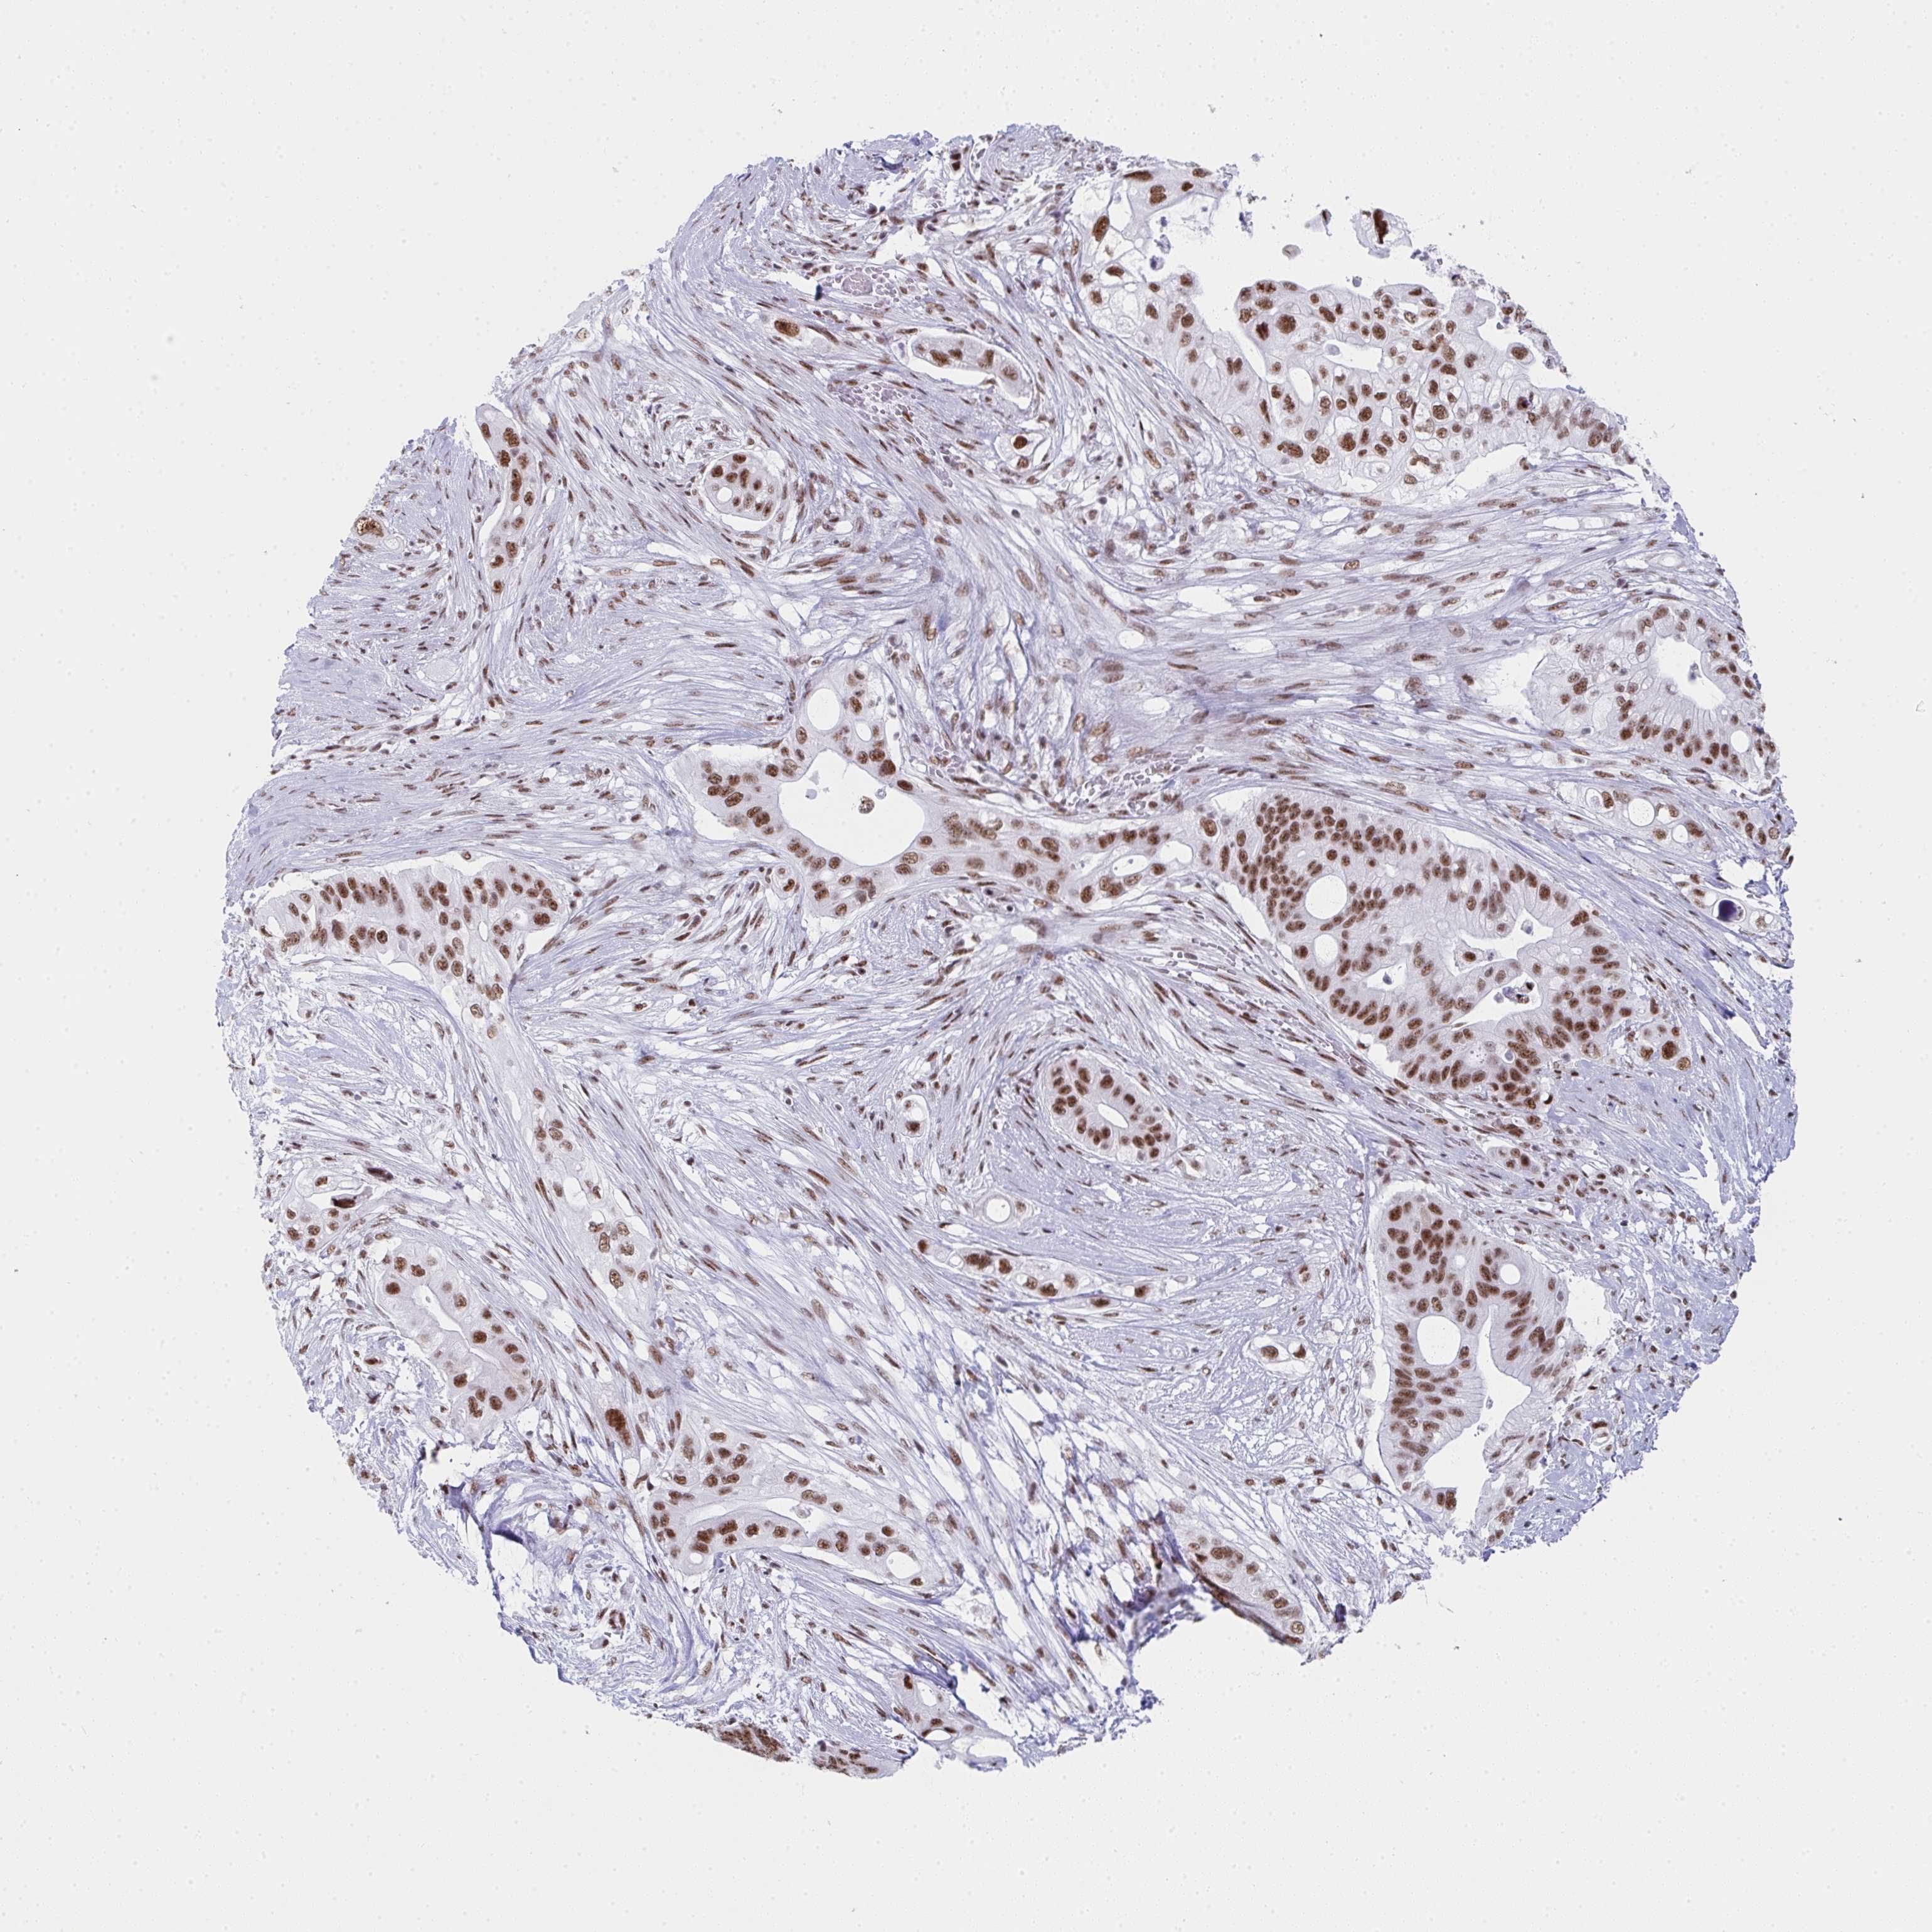

PANCREATIC CANCER - Protein expressioni

A mouse-over function shows sample information and annotation data. Click on an image to view it in a full screen mode. Samples can be filtered based on level of antibody staining by selecting one or several of the following categories: high, medium, low and not detected. The assay and annotation is described here.

Note that samples used for immunohistochemistry by the Human Protein Atlas do not correspond to samples in the TCGA dataset.

Antibody stainingi

Antibody staining in the annotated cell types in the current human tissue is reported as not detected, low, medium, or high, based on conventional immunohistochemistry profiling in selected tissues. This score is based on the combination of the staining intensity and fraction of stained cells.

Each image is clickable and will lead to virtual microscopy that enables deeper exploration of all samples and also displays staining intensity scores, fraction scores and subcellular localization as well as patient and tissue information for each sample.

Antibody HPA042050

Antibody HPA043516

Antibody CAB001718

Staining

High

Medium

Low

Not detected

Intensity

Strong

Moderate

Weak

Negative

Quantity

>75%

75%-25%

<25%

None

Location

Nuclear

Cytoplasmic/membranous

Cytoplasmic/membranous,nuclear

Adenocarcinoma, NOS